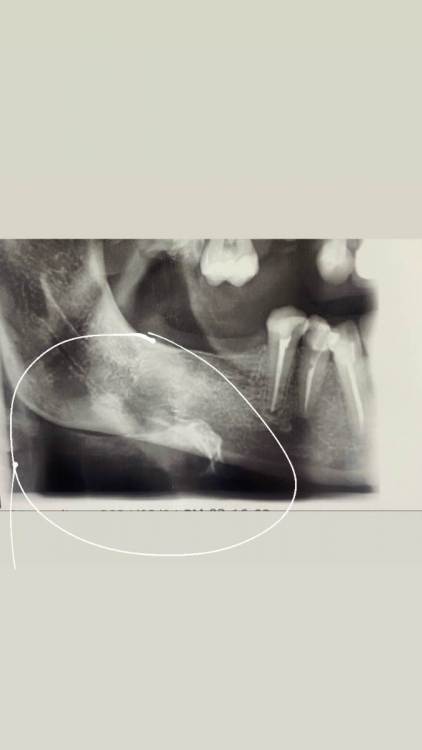

Екатерина77 Опубликовано 4 марта, 2024 Поделиться Опубликовано 4 марта, 2024 Доброго времени суток! Прошу совета. Сейчас занимаюсь подготовкой к протезированию и имплантации, посему как много что пришлось удалить. Последние пару месяцев возникает ощутимая боль при легком нажатии на угол нижней челюсти, когда допустим подпереть лицо рукой, или же просто лечь как - то неправильно, в последствии чего происходит легкое давление на этот угол. Примерно на снимке это вот эта область, обведена кружочком. Спрашивала у стоматолога, но она ничего сказать не смогла, сказала нужно показывать хирургу. Я так понимаю, что проблема все же есть. И прошу посмотреть ситуацию с корнями 4 и 5 - понимаю, что есть затемнение, но опять же - никто мне ничего про это не говорит. Каналы пломбированы более 8 месяцев назад. Благодарю за ответ Ссылка на комментарий

АнтонТЛТ Опубликовано 4 марта, 2024 Поделиться Опубликовано 4 марта, 2024 Ничего странного на снимке не вижу. Возможно есть гипертонус жевательной мышцы в этой области. То что белое на снимке, это наложение подъязычной кости. 2 Ссылка на комментарий